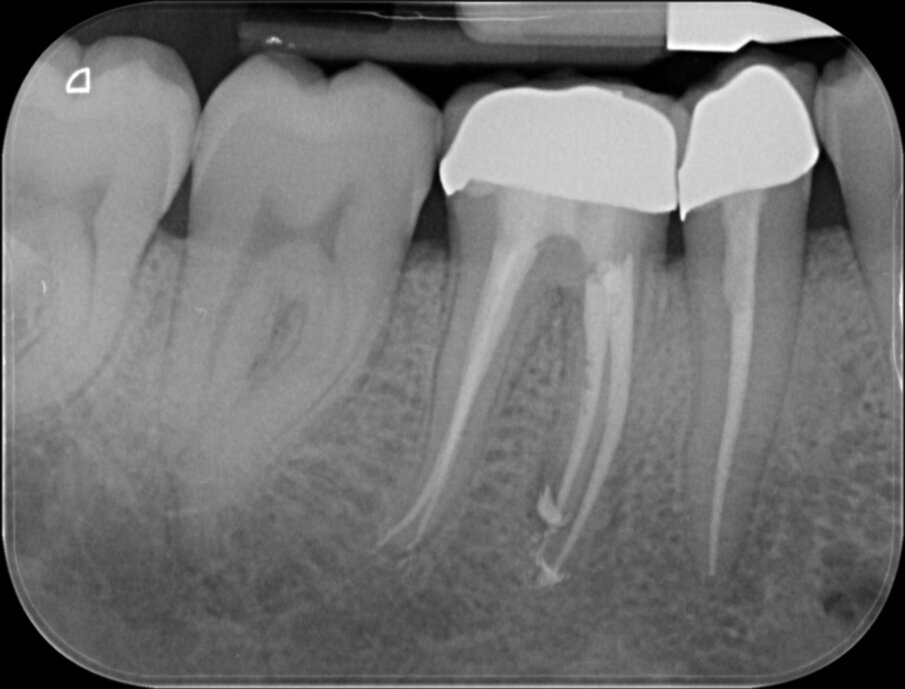

Vier jaar geleden meldde zich een patiënt in onze praktijk met heftige pijn in de regio 46. Na een blik op de bitewing en op de apicale röntgenopname (afbeelding 1 en 2) is de indicatie endodontische behandeling 46 snel gesteld.

De eindfoto’s stemmen tot optimisme. Röntgenologisch lijkt voldaan aan al de eisen die Schilder aan de vorm van geprepareerde kanalen stelde.

Er lijkt sprake van een gevuld systeem (afbeelding 3 en 4). De puffs in de laatste paar millimeter hebben geen klinische betekenis, maar zijn een normaal bijverschijnsel bij het obtureren van kanalen met een hydraulische obturatiemethode, gebruik makend van warme guttapercha. Hier kozen we voor Thermafil, wat een uitstekende reputatie heeft en de preferente vulmethode is van veel eminente clinici, zoals Buchanan en Ruddle. Vol vertrouwen presenteren we de resultaten aan de patiënt en we schrijven een brief aan de verwijzend tandarts dat het vervaardigen van een kroon nu kan geschieden zonder onaanvaardbare risico’s.

Vier jaar later bezoekt de patiënt wederom op verwijzing onze praktijk. Hij ondervindt wat ongemak van element 46 waar de tandarts 3 jaar geleden een kroon op heeft gemaakt. Bij kauwen is het element iets pijnlijk, iets wat hem sinds twee maanden opgevallen is. Afbeelding 5, 6 en 7 kunnen bevestigen wat de oorzaak is: Een opspelende laesie van endodontische origine (LEO) aan de mesio-buccale radix. Bittere teleurstelling aan onze zijde en een verdrietige patiënt.

De eindfoto’s zijn duidelijk: een iets vollere shape en wat nadrukkelijkere puffs. Fingers crossed! Over drie maanden weten we meer.